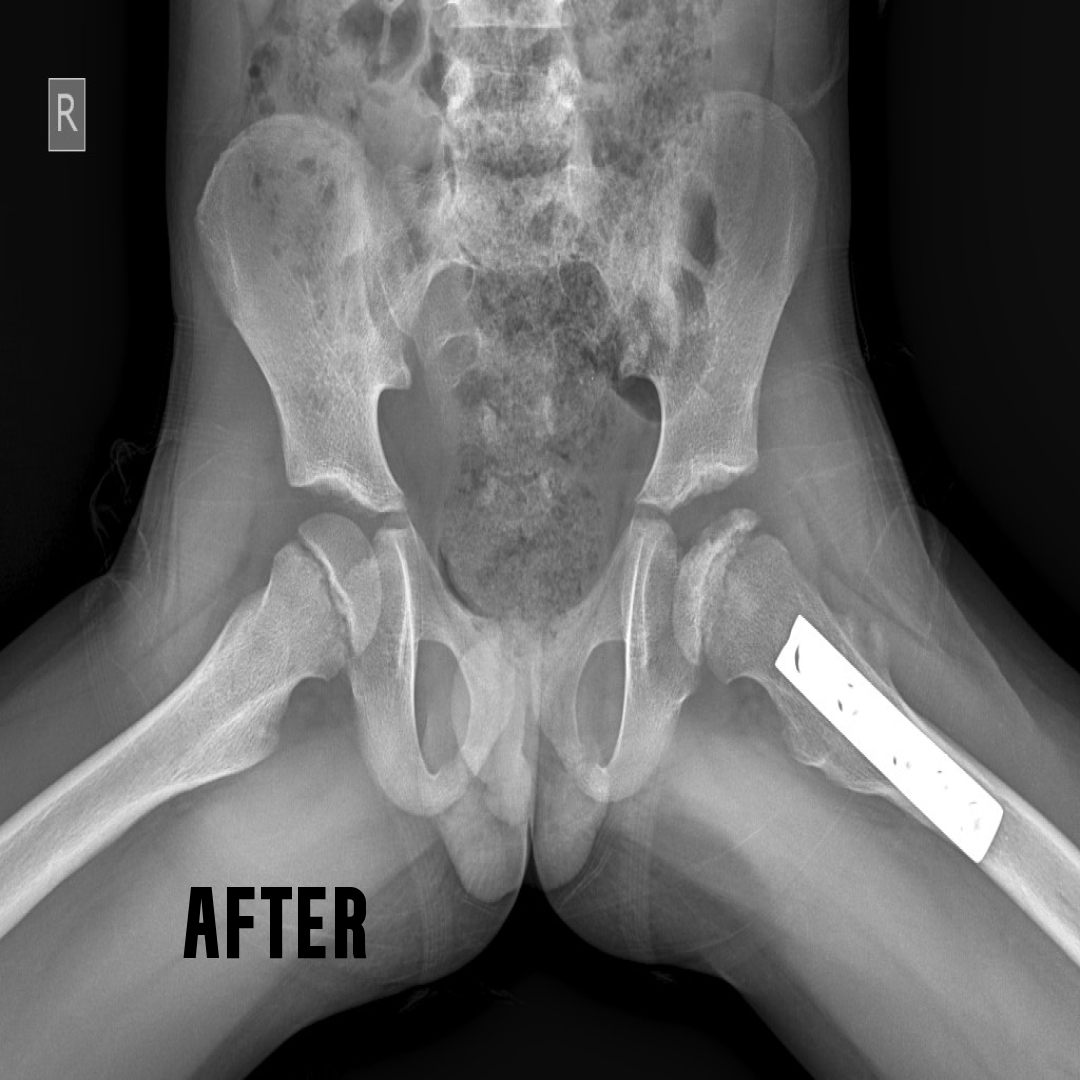

The hip joint may be partially or fully dislocated at birth. Diagnosis is made using ultrasound imaging. Every newborn should undergo an ultrasound examination of the hips, as this condition often remains undiagnosed at birth and only becomes noticeable when the child begins to walk—by which time, it is usually too late for simple correction.

Early detection is crucial. Immediate treatment after birth helps restore the hip to its normal position and function. Our sonologist can diagnose the condition at birth and promptly refer the child to our paediatric orthopaedic surgeon for appropriate management.

Our Ilizarov experts specialize in the elongation of short limbs. A detailed analysis of X-rays is required before starting the treatment.